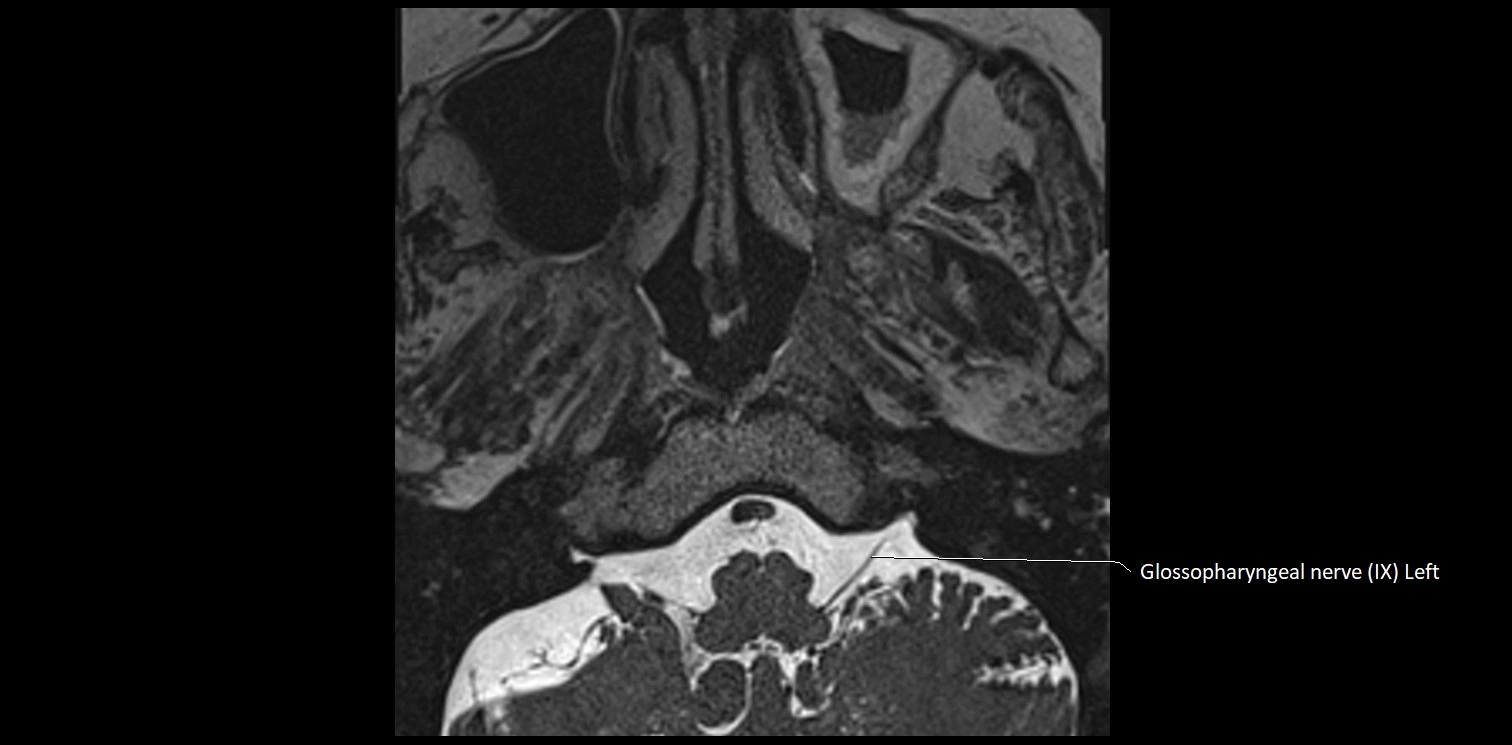

MRI Appearance

• The abducens nerve is a small, thin, linear structure

• Best visualized on high-resolution T2-weighted 3D MRI sequences (e.g., FIESTA or CISS)

• Seen as a hypointense (dark) line running from the brainstem at the pontomedullary junction, traversing the prepontine cistern, and entering Dorello’s canal under the petrosphenoidal ligament, then into the cavernous sinus, and finally the orbit

• May be challenging to visualize in standard MRI due to its small size

• Pathology may be inferred by absence, displacement, or enhancement of the nerve

MRI images

image